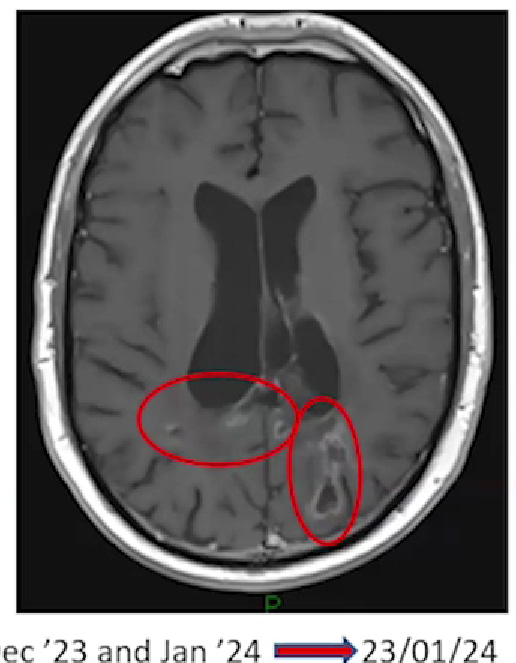

Duncan Campbell's brain scan

Read Duncan's (27 years) full story. Despite being diagnosed with glioblastoma in February 2021, he is living his best life, with a successful career and a fulfilling social life.

Secondary end points of the trial are to assess radiological evidence of cell kill (with MRI scans performed the day after SDT treatment and monthly for three further months), progression free survival and overall survival.